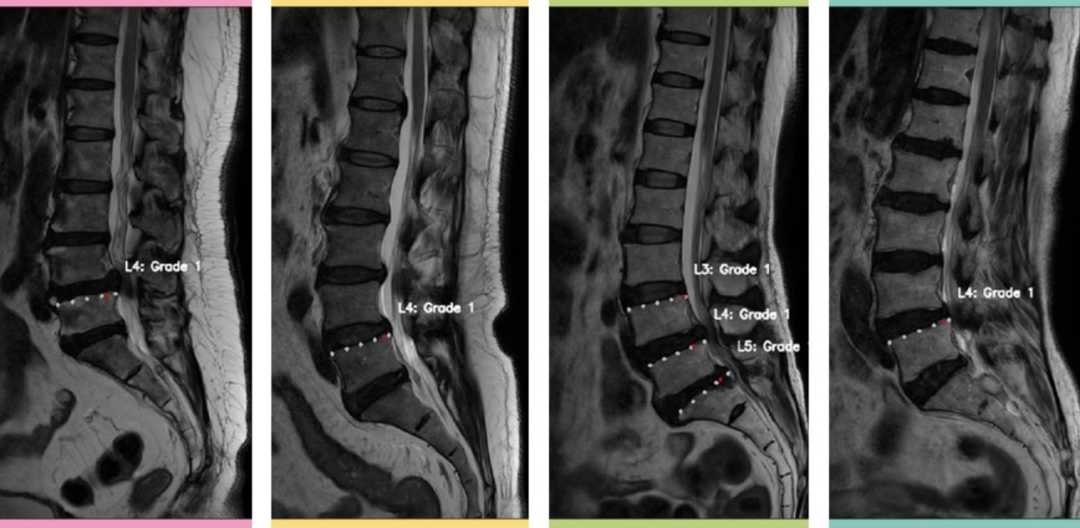

腰椎辅助诊断系统

滑脱定位检查方案

腰椎滑脱通常是由于先天性发育不良、创伤、劳损等原因造成相邻椎体骨性连接异常而导致的上位椎体与下位椎体部分或全部滑移,其表现通常为腰骶部疼痛、坐骨神经受累、间歇性跛行等情况,严重时还将影响正常生活。

好在通过检查进行早发现早治疗就能避免较多潜在危险,腰椎的MR检查是一种无创检查,其对腰椎的软组织、椎间盘、脊髓等组织的观察有优势,通常可进行腰椎滑脱的诊断,是一种较为常规的检测方案。

当然,腰椎滑脱也是一种常见的腰椎疾病,在诊断时若可结合人工智能进行多种腰椎疾病辅助诊断,或许可以减少医生的负担。

为了进一步提升诊断效率,本周吖吖查大佬通过深度学习的语义分割技术来协助检查,在该项目中的数据部分,为保证更高的分割性能,在预处理时保留每个腰椎数据中的中间几层,并把横突、棘突、骶骨(只保留骶一)和尾骨的标签去掉,接着通过强劲的语义分割套件PaddleSeg进行模型训练,最终模型mIoU达到了0.8868的较高水平,成功完成滑脱检测!